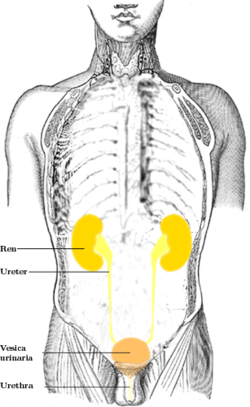

Ureter (Anatomical View) | |

Ureter (Schematic View) 1. Human urinary system: 2. Kidney, 3. Renal pelvis, 4. Ureter, 5. Urinary bladder, 6. Urethra. (Left side with frontal section), 7. Adrenal gland Vessels: 8. Renal artery and vein, 9. Inferior vena cava, 10. Abdominal aorta, 11. Common iliac artery and vein With transparency: 12. Liver, 13. Large intestine, 14. Pelvis | |

In human anatomy, the ureters are tubes made of smooth muscle fibers that propel urine from the kidneys to the urinary bladder. In the adult, the ureters are usually 25–30 cm (10–12 in) long and ~3–4 mm in diameter. Histologically, the ureter contains transitional epithelium and an additional smooth muscle layer in the more distal one-third to assist with peristalsis.

Structure

In humans, the ureters arise from the pelvis of each kidney, and descend on top of the psoas major muscle to reach the brim of the pelvis. Here, they cross in front of the common iliac arteries. They then pass down along the sides of the pelvis, and finally curve forwards and enter the bladder from its left and right sides at the back of the bladder.[1]:324–326 This is classically depicted as running "posteroinferiorly on the lateral walls of the pelvis and then curve anteromedially to enter the bladder". The orifices of the ureters are placed at the postero-lateral angles of the trigone of the bladder, and are usually slit-like in form. In the contracted bladder they are about 2.5 cm. apart and about the same distance from the internal urethral orifice; in the distended bladder these measurements may be increased to about 5 cm.

The junction between the pelvis of the kidney and the ureters is known as the ureteropelvic junction or ureteral pelvic junction, and the junction between the ureter and the bladder is known as the ureterovesical (ureter-bladder) junction. At the entrance to the bladder, the ureters are surrounded by valves known as ureterovesical valves, which prevent vesicoureteral reflux (backflow of urine).

In females, the ureters pass through the mesometrium and under the uterine arteries on the way to the urinary bladder.